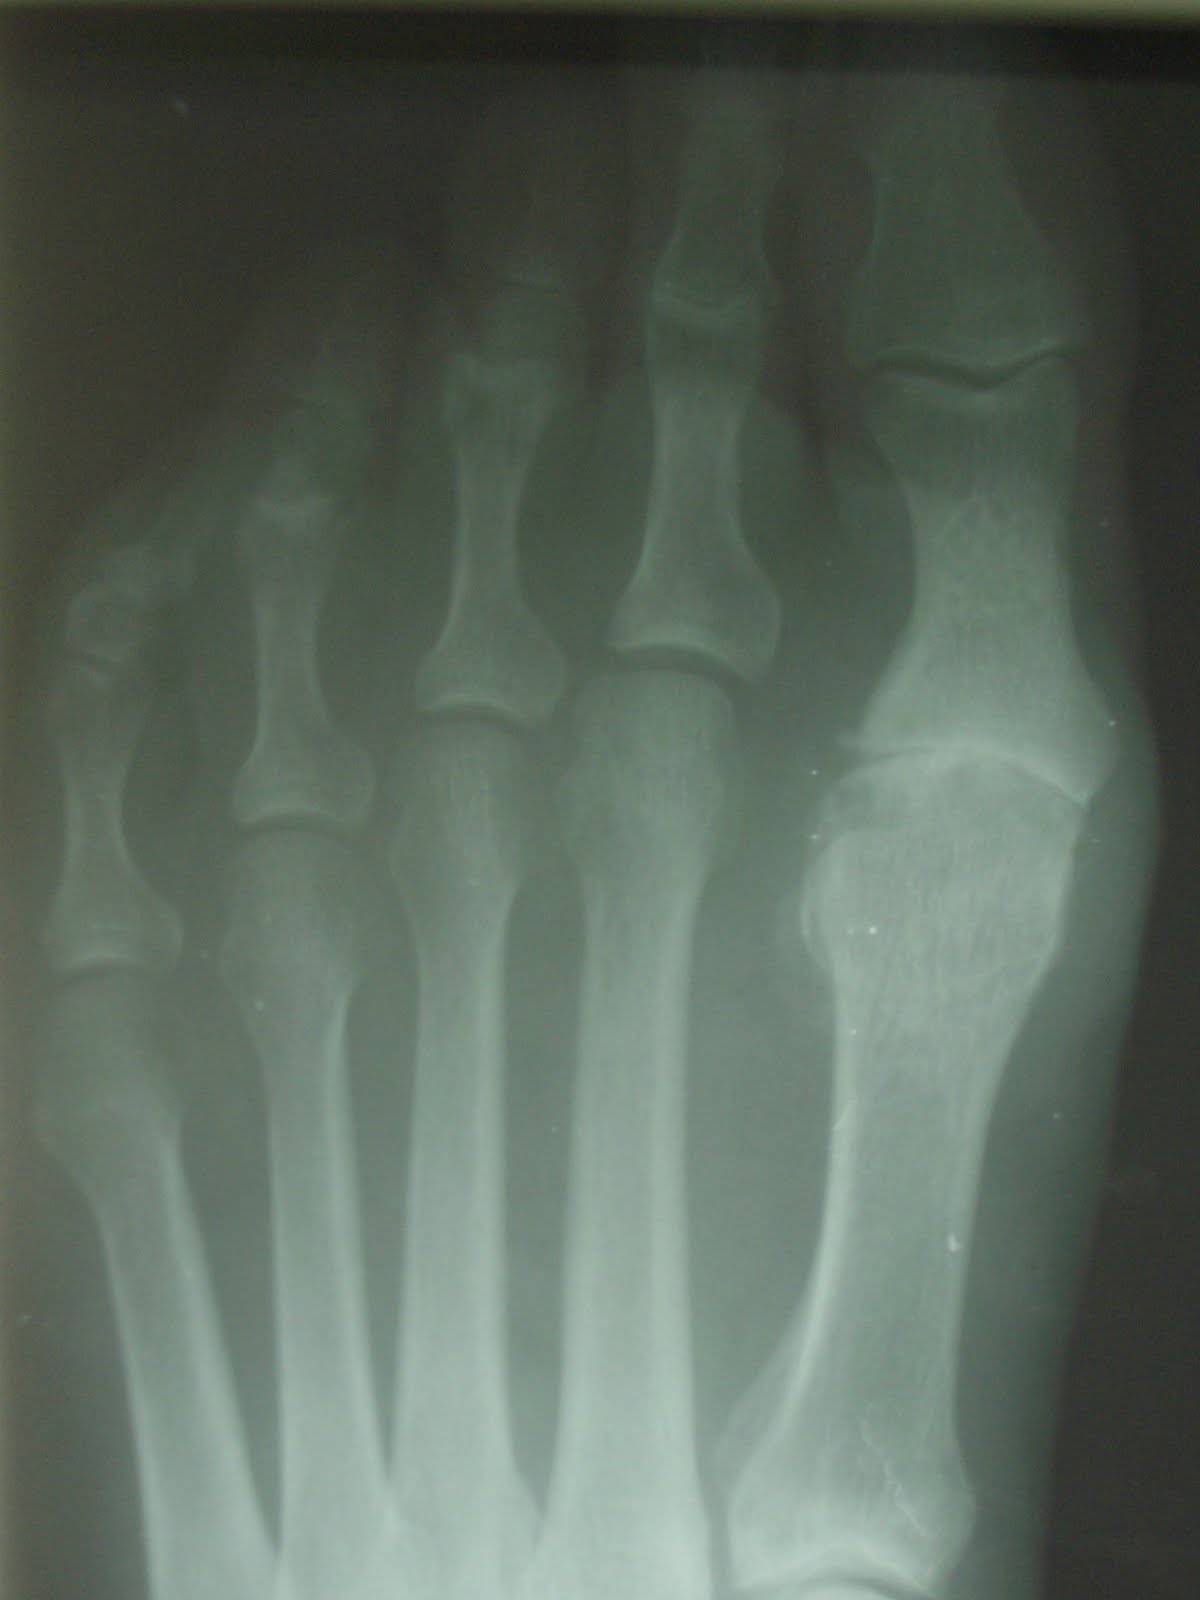

Una mujer viene con gran dolor en la articulación metatarsofalángica del primer dedo, presentando gran prominencia a nivel dorsomedial y diagnosticada por el médico de familia como de Hallux Valgus, o sea, juanete. Solo con explorarla físicamente se ve la gran limitación de movimiento que presenta, y en el estudio biomecánico no se le ve el valguismo por ninguna parte.

Le realizo estudio radiológico con el fluoroscopio y observamos las rebabas óseas en la cabeza del metatarsiano y en la base de la falange.

Esto es lo que confundió al médico de familia para diagnosticarlo como juanete ya que por su parte externa, presentaba gran abultamiento como se ve en la primera foto del caso.

En las radiografías que le hago, una oblicua y una D-P, vemos la disminución del espacio articular, los topes óseos, un posible comienzo de necrosis avascular en la cabeza del segundo metatarsiano,

subluxación de las articulaciones metatarsofalángicas de 2º y 3º radios, colapso articular en primera articulación con insuficiencia de primer radio, lo cual está provocando la patología en los radios centrales. El diagnóstico es de Hallux Rígidus y el tratamiento propuesto es cirugía, la cual acepta sin problemas quedando citada para operarla a mediados de Enero. La operación consistirá en colocarle un implante.